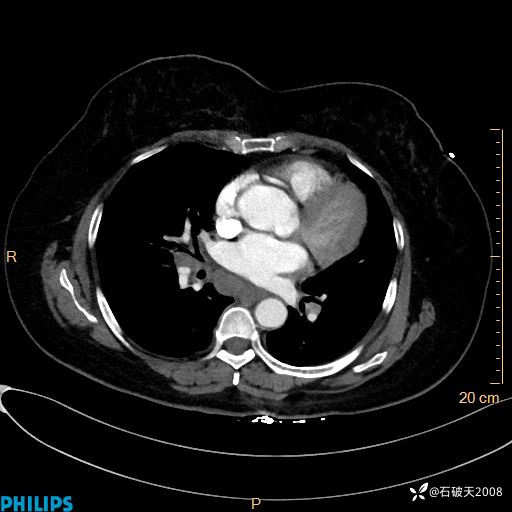

肺结节病?纵膈型肺癌?淋巴瘤?有点意思,欢迎围观

女 52岁 主 诉:咳嗽10余天,咳痰2天。

现病史:10余天前无明显诱因出现咳嗽,呈阵发性干咳,伴咽喉部发痒,无咽痛,无咳痰,无鼻塞、流涕、打喷嚏,无发热、畏寒、寒颤,无头痛、头晕,无胸闷、胸痛,无反酸、烧心,无腹痛、腹泻,无尿频、尿急,无皮疹等,在当地诊所求治,给予口服药物治疗(具体不详),病情无好转。遂在当地社区卫生服务中心开具口服药物治疗(具体不详),疗效欠佳。2天前出现咳痰,在我院门诊求治,行胸部CT提示肺部感染,建议住院,患者要求口服药物治疗,目前仍咳嗽、咳白色粘痰,白天量多,夜间自觉喉部喘鸣音,遂再次来院就诊,以“肺部感染”为诊断收入院。发病以来,神志清,精神可,饮食可,夜间睡眠差,大小便正常,近期体重无明显变化。

纵隔窗

动脉期